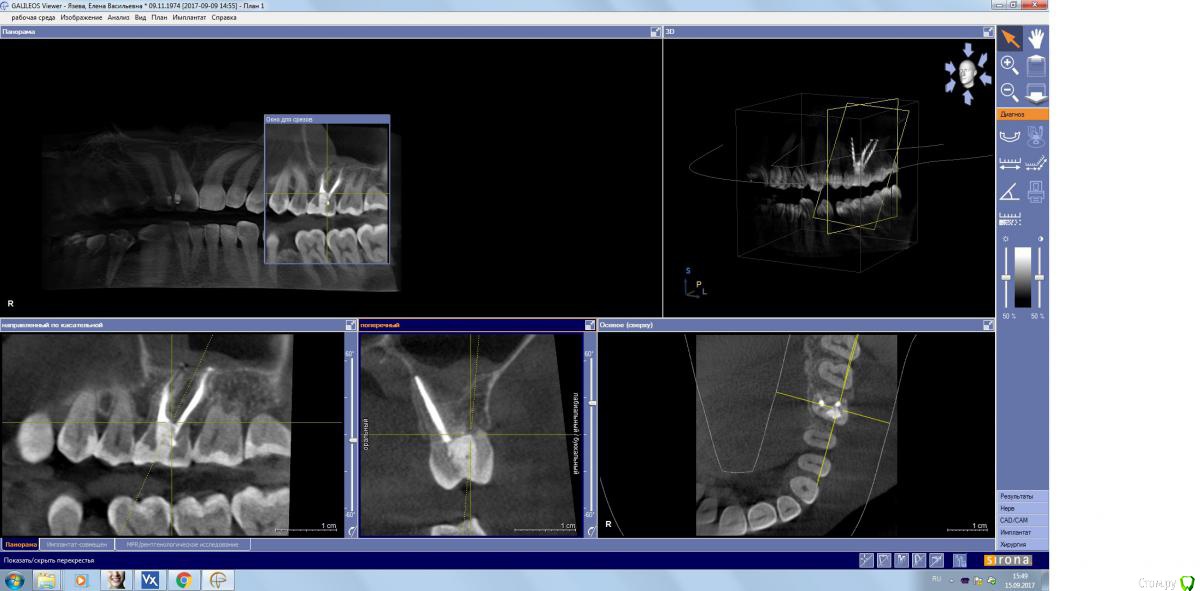

kamranchick Опубликовано 15 сентября, 2017 Поделиться Опубликовано 15 сентября, 2017 Господа, терапевт наш пролечил зуб, и болит пазуха уже месяц... сам зуб не болит, какой план действий? Ссылка на комментарий

kamranchick Опубликовано 15 сентября, 2017 Автор Поделиться Опубликовано 15 сентября, 2017 (изменено) Лор говорит хронический гайморит в стадии обострения, но провоцирует зуб, короче все как всегда... Изменено 15 сентября, 2017 пользователем kamranchick Ссылка на комментарий

kamranchick Опубликовано 15 сентября, 2017 Автор Поделиться Опубликовано 15 сентября, 2017 хотя бы узнать, это по нашей части, вернее мы виноваты или это со стороны лор что то, куда пациента определять... или опять в зуб лезть Ссылка на комментарий

parallax Опубликовано 16 сентября, 2017 Поделиться Опубликовано 16 сентября, 2017 Это пристеночно-гиперпластическая форма гайморита, застарелая хронь, которая появилась не вчера. Возможно, обострение спровоцировали паффы (куда ж без них). Я думаю, стоматологи тут не при чём. Хотя ЛОРики всегда обвиняют нас (скоро вменят убийство Кеннеди). В каналы лезть больше не надо, отправляйте в ЛОР отделение, лечение этого гайморита хирургическое. 1 Ссылка на комментарий

ger_berra Опубликовано 2 октября, 2017 Поделиться Опубликовано 2 октября, 2017 Решётчатый лабиринт посмотрите. Там часто много чертей сидит. Ссылка на комментарий